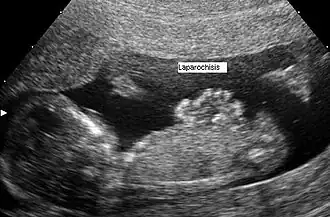

Die Gastroschisis (deutsch auch Bauchspalte genannt, griechisch γαστροσχίσις, von gástro~, „Magen~, Bauch~“ und s-chísis/s-chísma, „die Spaltung“) ist eine vorgeburtlich (pränatal) spontan entstehende meist rechts vom Nabel gelegene Fehlbildung der Bauchwand mit Vorfall von Darmschlingen beim Fetus. Die Besonderheit wird oft mittels Feinultraschall im Rahmen der Pränataldiagnostik diagnostiziert und ist nachgeburtlich (postnatal) in den meisten Fällen operabel.

Bereits vorgeburtlich kann die Gastroschisis im Ultraschall festgestellt werden.